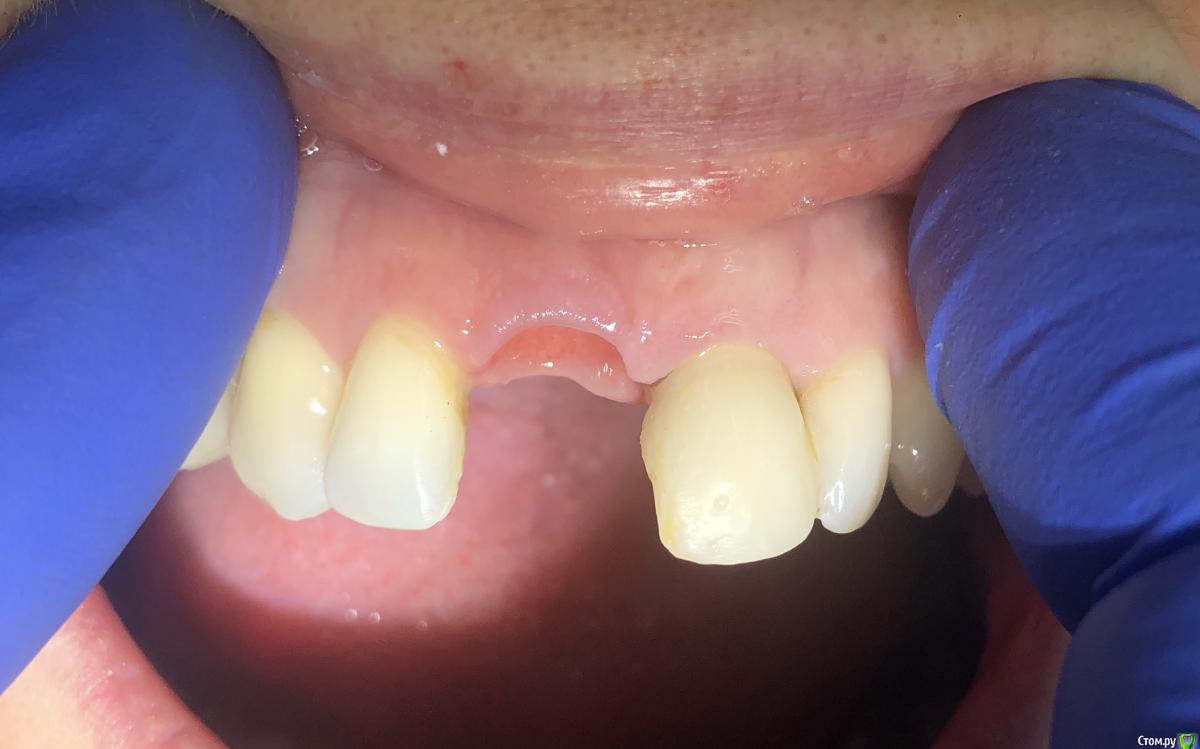

Александр07 Опубликовано 26 июня, 2020 Автор Поделиться Опубликовано 26 июня, 2020 Коллеги, скидываю фото проделанной работы, прошло около 1.5 мес, есть результат, спасибо за помощь, если какие то замечания /советы есть пишите 4 Ссылка на комментарий

колесников Опубликовано 26 июня, 2020 Поделиться Опубликовано 26 июня, 2020 (изменено) Здравствуйте! Не видел этого поста раньше,бегло посмотрел. Определенно проблема была в выборе высоты абатмент и объёме реставрации. Вы убрали композит максимально в основании-это хорошо,но абатмент оставили прежний. Следовало взять новый с высотой уступа 4-5 мм. Край коронки пришеечный следует опустить ниже,иначе десна опять отскочит. И переход слелайте на плавный а под углом,так называемый балкон. Потом будет что отдавить. По Масана сосочек сделали это хорошо и правильно,но с такой реставрацией опасно,мало место лоскуту. К счастью кажется все живы. На данном этапе рекомендую пропилить балкон и этим ограничится. Изменено 26 июня, 2020 пользователем колесников Ссылка на комментарий

Александр07 Опубликовано 27 июня, 2020 Автор Поделиться Опубликовано 27 июня, 2020 Здравствуйте! Не видел этого поста раньше,бегло посмотрел. Определенно проблема была в выборе высоты абатмент и объёме реставрации. Вы убрали композит максимально в основании-это хорошо,но абатмент оставили прежний. Следовало взять новый с высотой уступа 4-5 мм. Край коронки пришеечный следует опустить ниже,иначе десна опять отскочит. И переход слелайте на плавный а под углом,так называемый балкон. Потом будет что отдавить. По Масана сосочек сделали это хорошо и правильно,но с такой реставрацией опасно,мало место лоскуту. К счастью кажется все живы. На данном этапе рекомендую пропилить балкон и этим ограничится.С высотой да, выше надо было , на постоянной учтём , по балкону принцип понятен, - больше места для транса, но все же времянки рекомендуют плавными делать, без резких переходов, поэтому такой вопрос если выпиливать максимально места для тр-та то когда переводить временную коронку на плавный дизайн , через месяц где-то когда транс приживется и стабилизируется первично ? Ссылка на комментарий

колесников Опубликовано 27 июня, 2020 Поделиться Опубликовано 27 июня, 2020 Через 2 недели. Но можно и месяц Ссылка на комментарий